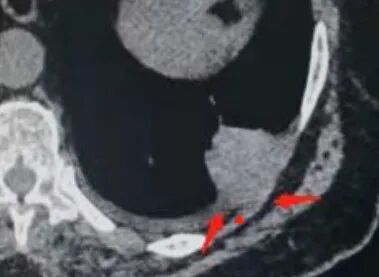

糊墙:肺内病灶不侵犯壁层胸膜或以外,与壁层胸膜相对而言分界清楚。

栽赃:病灶侵入壁层胸膜及胸膜外脂肪间隙、胸壁其他结构等,相对在病灶中央区域,与胸膜分界不清。

南边:看肺内病灶与胸膜分界清,增强后强化不一致,需要综合分析。

这是糊墙。

这就栽赃。都突到外面去了。

南边:一般这类侵袭,是中央地带毛刷状延伸到胸膜内。

我只是邓较瘦:南大这个我感觉局部似乎是栽赃呢 箭头那里是啥?

南边:栽赃是这样过去的,中间不会脂肪间隙清晰。